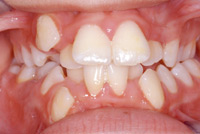

Ein sogenannter Engstand der Zähne entsteht

dann, wenn die Babys nur mit der Flasche

ernährt wurden und der Saugvorgang so

einfach war, dass er kein grosses

Kieferwachstum provozierte. Dann haben die

Zähne später keinen Platz und das Gebiss

sieht aus wie ein Birchermüesli.

Zahnfehlstellung Engstand

Engstand nennt sich der Platzmangel der Zähne bei

einem zu kleinen Kiefer [6]. Kiefer werden zu klein

-- durch zu wenig Wachstumsreiz, wenn das Kind nicht

gestillt wird, sondern immer die Flasche bekommt [2]

-- durch Verlust der Milchzähne im frühen Kindesalter

durch Flaschenkaries, so dass die Milchzähne ihre

Rolle als "Platzhalter"nicht mehr wahrnehmen können

[5].

Engstand der Zähne, eine Frontalansicht |